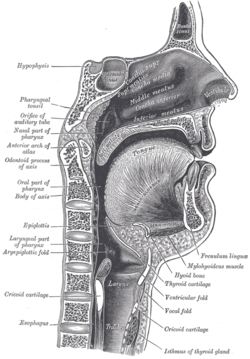

Lateral wall of nasal cavity. Sagittal section of nose mouth, pharynx, and larynx.

Sagittal section of nose mouth, pharynx, and larynx. Outline of bones of face, showing position of air sinuses.